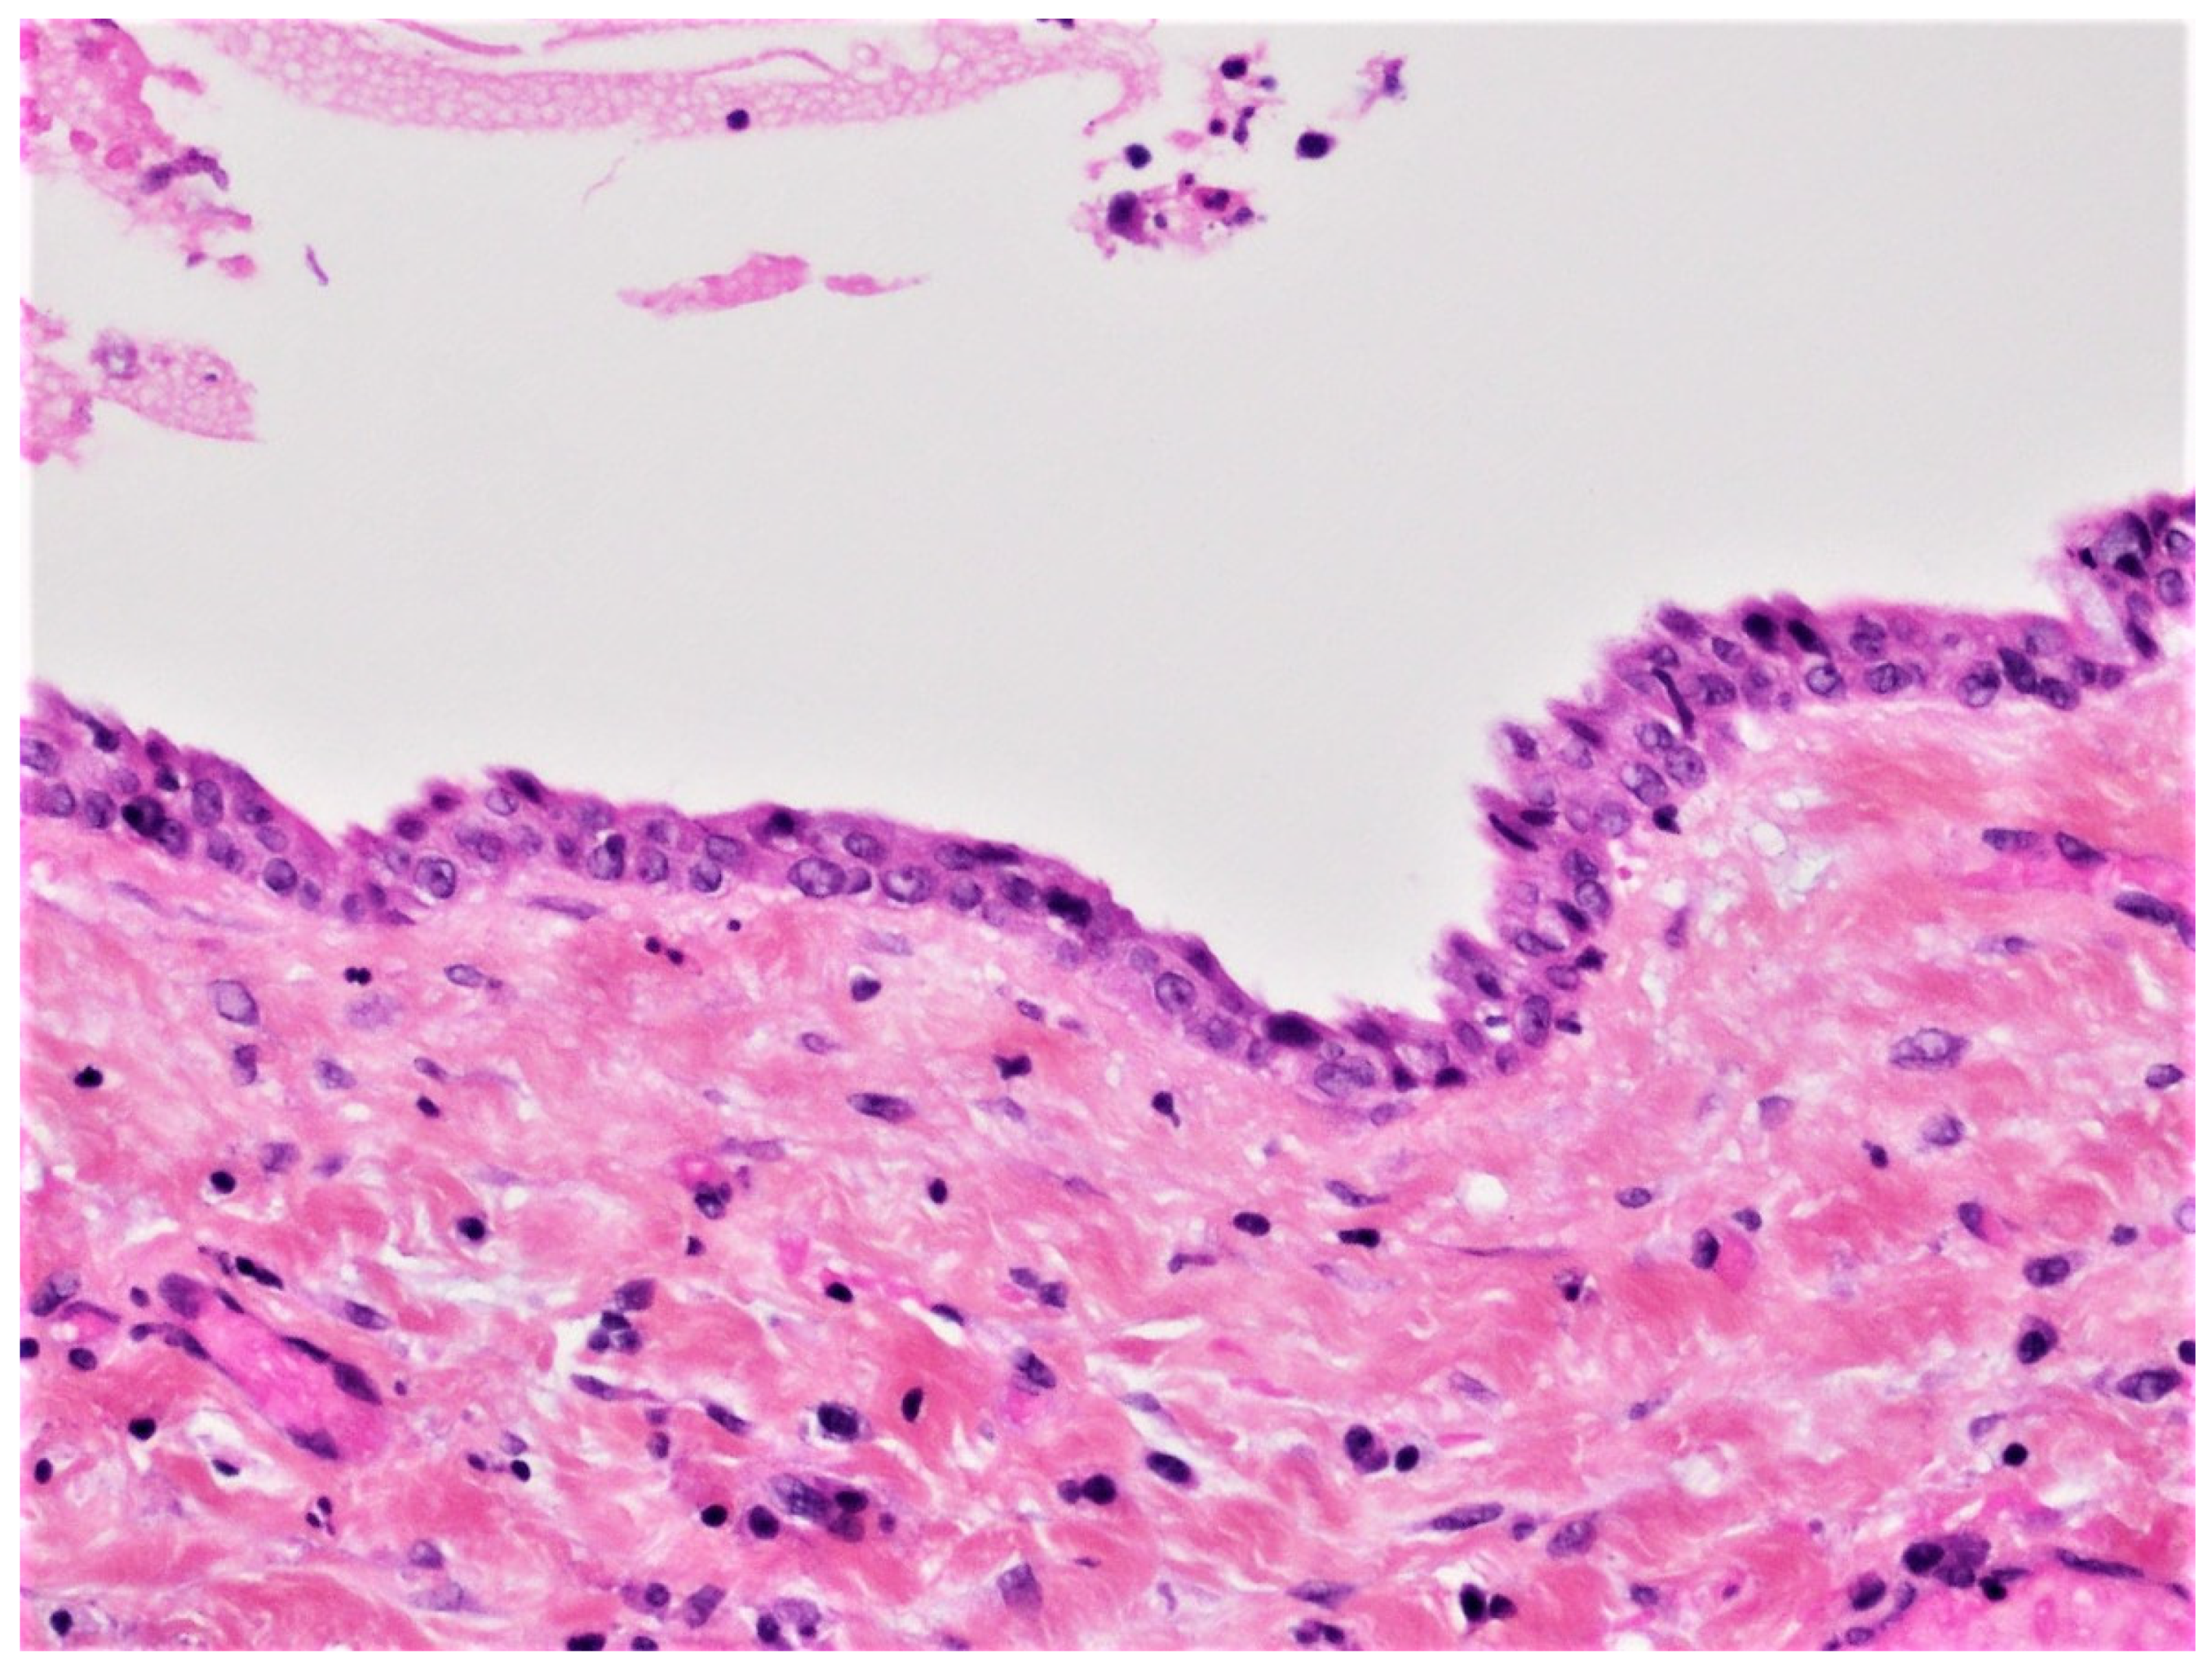

Figure 3.

Histopathological examination of the enucleated specimen from case #1 showing an uninflamed fibrous cyst wall lined by a thin cuboidal epithelial lining (H&E, ×40).

DC is the second most common odontogenic cyst occurring in association with an unerupted tooth. It develops from the accumulation of fluid between the reduced enamel epithelium of the dental follicle and the crown of an unerupted tooth (Figure 14). The microscopic features of DC are dependent whether it is not inflamed or inflamed [,,,]. In the case of non-inflamed DC, the epithelial lining is formed by two to four layers of cuboidal/squamous non-keratinizing cells without rete ridges and a flat epithelium-connective tissue interface (Figure 3). The cyst wall consists of fibrous or fibro-myxoid tissue containing considerable glycosaminoglycan ground substance. Small islands or cords of inactive-appearing odontogenic epithelial rests are usually present within the connective tissue.